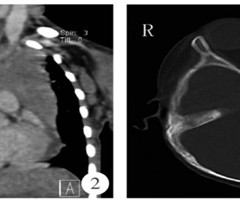

青少年自发性纵隔气肿影像学表现与临床分析

【摘要】目的目的 探讨青少年自发性纵隔气肿(SPM)的影像学表现与临床分析。方法回顾性分析31例临床明确诊断的青少年SPM患者为本次的研究对象。患者均接受数字X线摄影(DR)或/和多排螺旋CT影像学检查,重点分析影像学结果和患者临床特点。结...